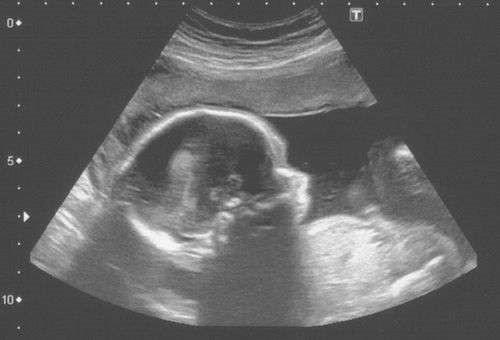

O nascituro possui direitos reconhecidos pela legislação brasileira, como o direito à vida, saúde, alimentação, educação, herança e dignidade. É responsabilidade do Estado, da sociedade e da gestante garantir a proteção e respeito aos direitos do nascituro, visando construir uma sociedade mais justa e igualitária.